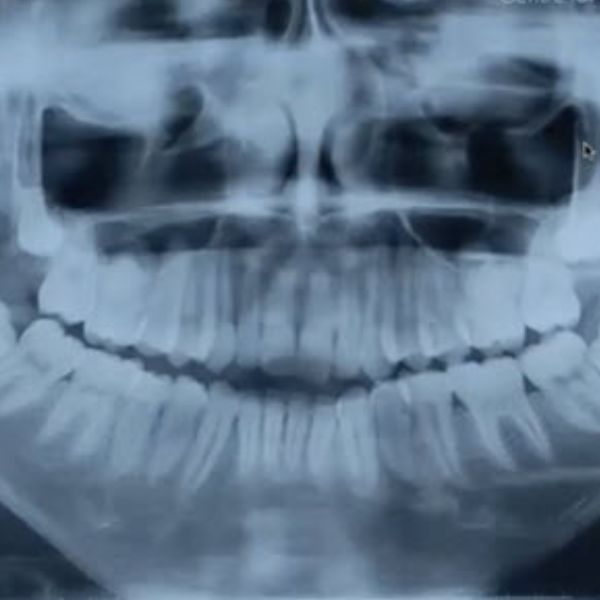

The goals of pediatric Temporomandibular Joint (TMJ) reconstruction are to maintain pain-free mouth opening and prevent re-ankylosis or heterotopic bone formation. We are doing these techniques in small children, but small children will grow. This means adopting a technique that will grow with the children, that would limit asymmetry. There are considerations to differing techniques to TMJ reconstruction in children.

Obviously, children who have undergone TMJ surgery at a very young age will have a small mandible. This decreases the airway space and predisposes these patients to obstructive sleep apnea later on, so we also need to increase the airway space.

We must also consider TMJ ankylosis, a very challenging area for a TMJ joint reconstruction in children.

Let us first look at what happens when you do no reconstruction in cases where the children are operated on, or diseases of the temporomandibular joint ankylosis, let's say temporomandibular joint. If we consider a case of bilateral ankylosis, one year postoperative, the patient will probably be doing fine, and function is restored. Even three or ten years on, we might say the same.

But what has really happened is that while the mouth opening is adequate, no catch-up growth has happened, even when the functional matrix is restored as per Moss’s theory. Functional treatment has happened, but the growth has not, so aesthetics is compromised.

Another reason why reconstruction should be done is osteoarthrotomy, or a lack of growth in the condyle, if you don’t reconstruct them. We have shown that in two of our publications, where there is a loss of vertical height and the mandible rotated backwards. This pushes the tongue into a more posterior position, causing obstructive sleep apnea. These cases are detailed in the January 2021 and December 2021 Journal of Oral Maxillofacial Surgery.